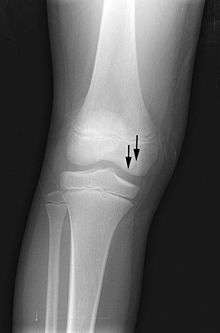

X-ray images of avascular necrosis in the early stages usually appear normal. In later stages it appears relatively more radio-opaque due to the nearby living bone becoming resorbed secondary to reactive hyperaemia.[1] The necrotic bone itself does not show increased radiographic opacity, as dead bone cannot undergo bone resorption which is carried out by living osteoclasts.[1] Late radiographic signs also include a radiolucency area following the collapse of subchondral bone (crescent sign) and ringed regions of radiodensity resulting from saponification and calcification of marrow fat following medullary infarcts.

Radiography of total avascular necrosis of right humeral head. Woman of 81 years old with diabetes of long evolution.